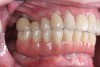

Fig 1. Preoperative retracted facial view of a 61-year-old man who presented with a failing maxillary hybrid prosthesis.

Figure 1

A 61-year-old man residing in Ohio was referred to the author's New Jersey practice for diagnosis and treatment of a failing maxillary hybrid prosthesis (Figure 1). The patient's maxillary teeth had been extracted in June 2011, when five implants were placed. Restoration of the maxillary arch was completed in April 2012. Aside from a sensitivity to aspirin and taking 20 mg of atorvastatin per day, the patient's medical history was negative.